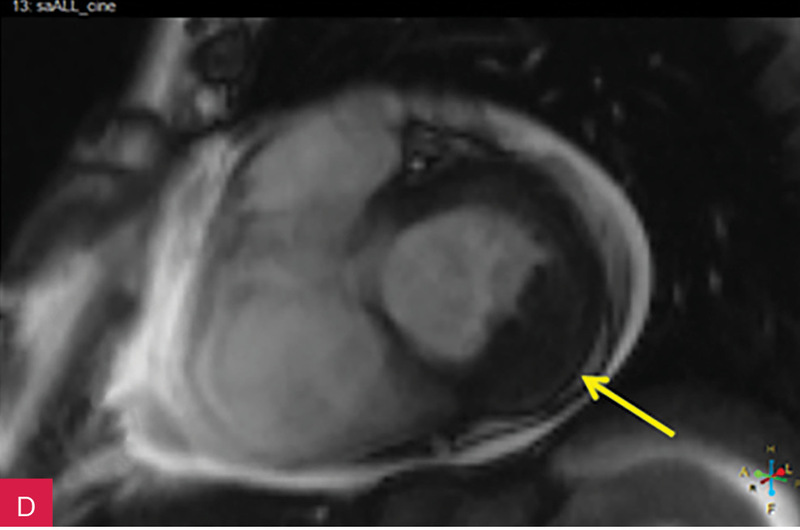

Rycina 7A-D. Obrazy rezonansu magnetycznego w osi krótkiej na wysokości pierścienia mitralnego: czarnej krwi T1-zależne TSE (A); czarnej krwi T2-zależne HASTE (B); T1-zależne echa gradientowego dynamicznie podczas podawania środka kontrastowego (C); sekwencja SSFP, pojedynczy obraz w osi krótkiej (D). W dolno-bocznej części pierścienia mitralnego od strony światła lewej komory zmiana (strzałki) niskosygnałowa we wszystkich ważeniach sygnału

W celu weryfikacji zmiany i oceny charakterystyki tkanki wykonano CMR,

w którym stwierdzono w dolno-bocznej części pierścienia mitralnego od strony światła lewej komory zmianę odpowiadającą morfologicznie CCMA, obejmującą 7,3 cm obwodu pierścienia mitralnego, o grubości w osi krótkiej do 25 mm, w osi długiej do 21 mm; zmiana ulegała brzeżnemu wzmocnieniu kontrastowemu i powodowała ograniczenie ruchomości tylnego płatka zastawki mitralnej, obejmowała struny ścięgniste mięśnia brodawkowatego tylno-przyśrodkowego. Ponadto uwidoczniono znacznie powiększone przedsionki z istotnym włóknieniem – jak w restrykcji (ryc. 7, 8).